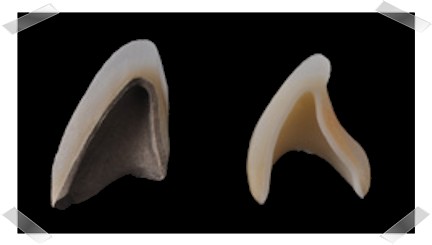

Pressləmə keramika texnologiyası təbii dişlərə ən yaxın görüntü verə bilən çox möhkəm, yükgül və son dərəcə gigiyenik olan, yüksək dərəcədə kristallaşan Litium disilikat (LiSi2) keramikanın istənilən formada hazırlanmasına əsaslanır. Müxtəlif rənglərdə hazırlanan keramika blokları xüsusi fırınlarda əridilir və əvvəlcədən hazırlanan diş qapaqı formalarına yüksək təziq altında axıdılır. Bu formalarda kristallaşan keramika çox dəqiq və incə qapaqların (koronkaların) hazırlanması ilə nəticələnir.

Pressləmə keramika texnologiyası təbii dişlərə ən yaxın görüntü verə bilən çox möhkəm, yükgül və son dərəcə gigiyenik olan, yüksək dərəcədə kristallaşan Litium disilikat (LiSi2) keramikanın istənilən formada hazırlanmasına əsaslanır. Müxtəlif rənglərdə hazırlanan keramika blokları xüsusi fırınlarda əridilir və əvvəlcədən hazırlanan diş qapaqı formalarına yüksək təziq altında axıdılır. Bu formalarda kristallaşan keramika çox dəqiq və incə qapaqların (koronkaların) hazırlanması ilə nəticələnir.